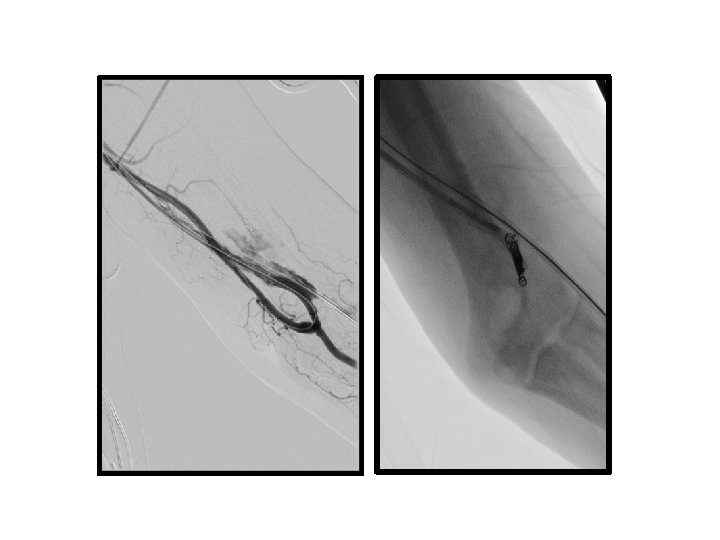

PTA sırasında oluşan venöz komplikasyonlar

• venöz rüptür (%2, 1 - 20) • akut / gecikmiş rüptür • minimal ekstravazasyon ve küçük hematom → damar duvar bütünlüğünde belirgin bozulma ve masif hematom • venöz diseksiyon

venöz rüptür • • • Manuel kompresyon Balon tamponat Stent yerleştirme Embolizasyon Cerrahi ligasyon

venöz rüptür

Venöz diseksiyon